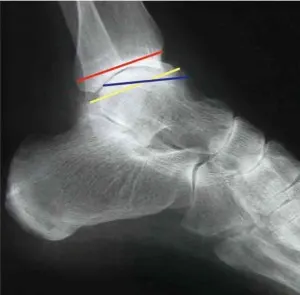

Le bilan d’imagerie préopératoire comporte des radiographies de la cheville de face et de profil en charge et une incidence de l’arrière-pied cerclé de Méary. Un bilan scannographique est également habituellement réalisé pour préciser l’importance de la dégradation arthrosique des articulations TT, ST, médio-tarsienne et anticiper les difficultés d’accès arthroscopique à l’articulation (ostéophytes).

Il s’agit principalement des séquelles des fractures thalamiques du calcanéus (figure 20.9) et du processus latéral du talus et plus rarement de séquelles d’entorses graves péri-taliennes ou d’arthrites ST.L’arthrodèse arthroscopique de l’articulation ST a été initialement décrite par un abord latéral et postéro-latéral [9]. Elle a été ensuite été popularisée par Van Dick [11] qui proposait un abord arthroscopique exclusivement postérieur.Le bilan préopératoire comprend des radiographies de face et de profil en charge de la cheville. Un examen TDM peut être utile pour prévoir la difficulté d’accès à l’articulation ST postérieure (figure 20.10).